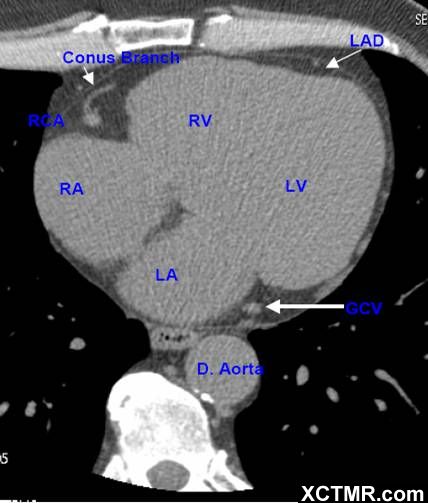

LA - Left Atrium 左心房

RA - Right Atrium 右心房

LV - Left Ventricle 左心室

RV - Right Ventricle 右心室

D. Aorta-Descending Aorta 降主动脉

LAD - Left Anterior Descending Artery 左前降支

RCA - Right Coronary Artery 右冠状动脉

Conus Branch 右动脉圆锥支

GCV –Great Cardiac Vein 心大静脉